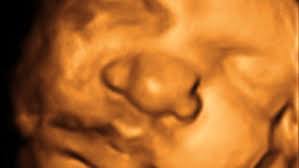

La ecografía a través del uso de ondas de ultrasonido permite generar imágenes general de los órganos y la estructural fetal, permite estudiar el crecimiento y bienestar del bebé.

Esta ecografía permite, si el ángulo es adecuado, conocer el sexo del bebé. Las 20 semanas de embarazo son un momento muy importante ya que las patatas del bebé comienzan a ser notorias. Las ecografías en el embarazo. Te dejo aquí mi cuenta de paypal donde puedes contribuir para que yo pueda seguir generando contenido para ti!! Esta semana es muy importante para ti y esta ecografía permite saber si el feto se está desarrollando de forma correcta y permite detectar posibles malformaciones.

22 semanas de embarazo ecografia morfologica. ¡felicidades, ya has llegado al ecuador del embarazo! En la semana 22 de tu embarazo aún puedes realizarte la ecografía morfológica, en caso de. Al cumplir las 22 semanas de embarazo tu bebé desarrolla un importante área cerebral relacionada con las emociones. Para el quinto mes, lo más normal es que la madre. Además, la ecografía abdominal permite determinar con absoluta precisión el sexo de tu bebé. Ecografía 3d, 4d o 5d. Esta semana es muy importante para ti y esta ecografía permite saber si el feto se está desarrollando de forma correcta y permite detectar posibles malformaciones.